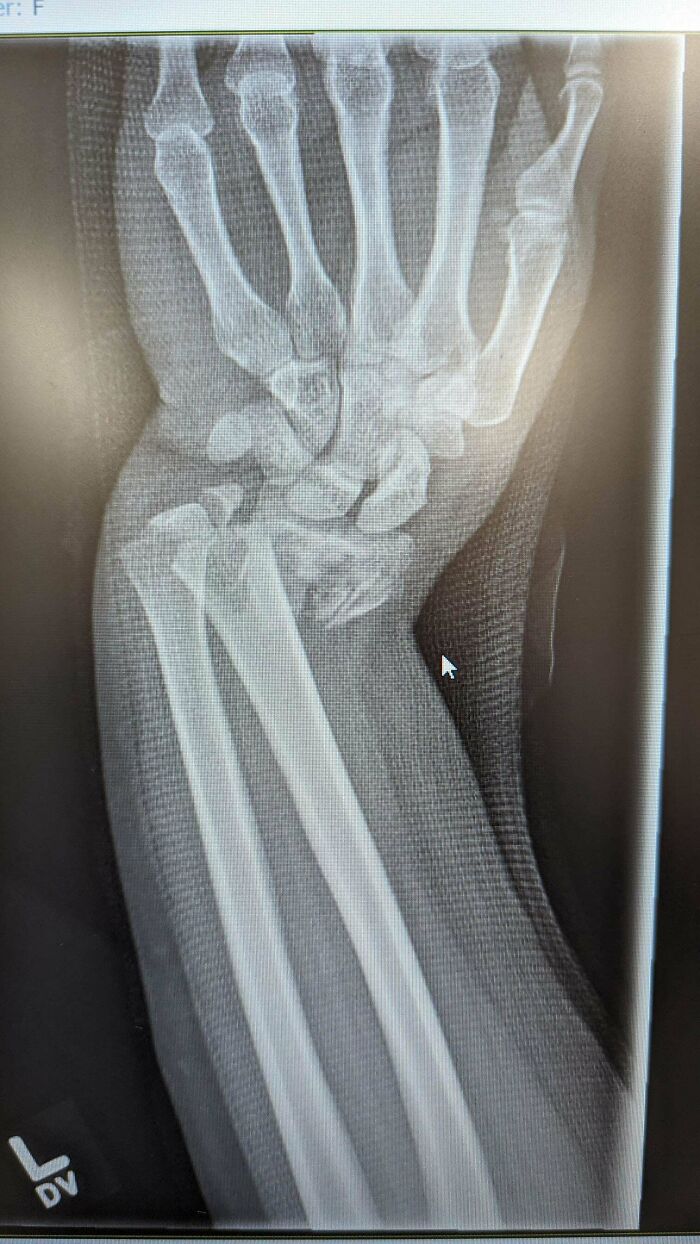

Not The Greatest Start To 2024 For Me